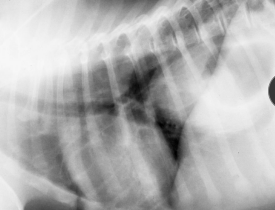

Gastric Foreign Bodies

Et: Obx at pylorus or intestines, Metal toxicity (zinc or lead), pressure necrosis, perforation

Post-1983 pennies contain zinc

Cs: acute vomiting, Obx

Dt: metabolic alkalosis (pyloric outflow obx), repeat rads before endoscopy

LAB: Hypochloremic, hypokalemia metabolic alkalosis with obstruction

Tx: Apomorphine (sm + smooth), endoscopic removal, Sx

Dont induce: Sharp, caustic, Obx, shock, airway compromise, corrosives